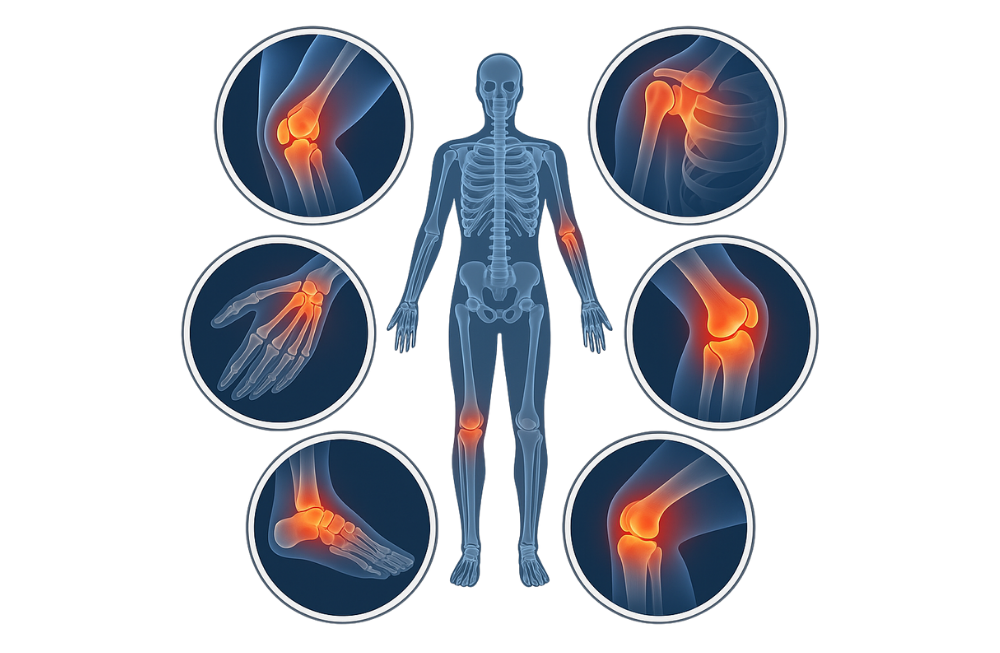

Why Choose Our Orthopedic Doctors?

Our orthopedic doctors combine advanced techniques with compassionate care to restore mobility and relieve pain effectively.

Who is it for?

- People with:

- Joint Pain

- Arthritis or Osteoporosis

- Fractures & Sports Injuries

- Back, Neck & Knee Pain

Risks of

Not Opting for Treatment?

- Chronic Pain

- Restricted Movement

- Decline in Daily Functioning

Q. What factors contribute to Orthopaedics diseases?

Orthopaedic diseases can be caused by a variety of factors, including aging, genetic predisposition, lifestyle choices, sports injuries, poor posture, obesity, and trauma from accidents. Common conditions include arthritis, osteoporosis, fractures, ligament tears, and spinal disorders.

Q. What are the latest advances in Orthopaedics treatments available at Wockhardt Hospitals?

Wockhardt Hospitals offers cutting-edge orthopaedic treatments including robotic joint replacement surgeries, minimally invasive arthroscopy, advanced spinal procedures, sports injury management, and biological therapies like PRP (Platelet-Rich Plasma). Our team of experienced orthopedic surgeons uses state-of-the-art technology to ensure precision, faster recovery, and improved outcomes.